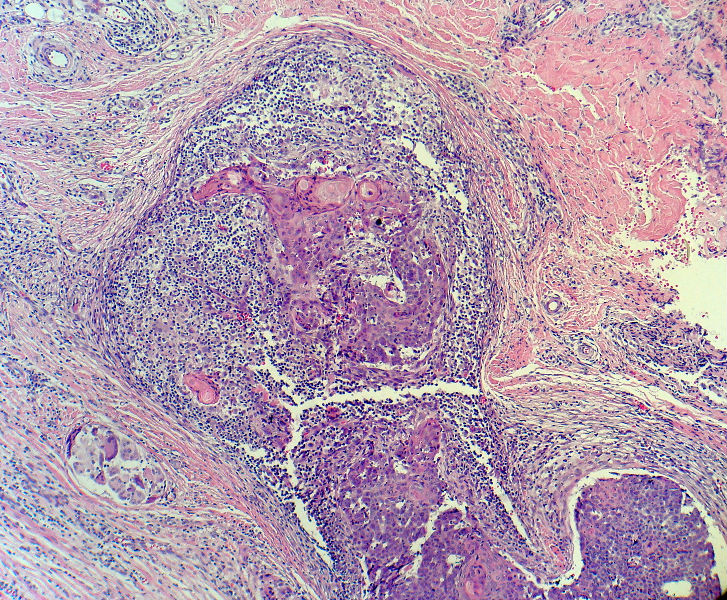

后枕部肿物

男,49岁,后枕部肿物3年,偶有破溃出血。

大体:皮肤半球形隆起,大小约2.3×2厘米,高出皮表0.8厘米,切面灰白,质地细腻。

似乎既有腺样结构,也有角化珠形成,还有细胞团内的粉刺样坏死。

有坏死、囊肿、钙化及胆固醇样裂隙等结构

考虑外毛根鞘肿瘤,局部癌变。

大部分区域看着象基底细胞癌,后面几张(11-14)看着象是鳞癌。综合考虑基底细胞样鳞癌。